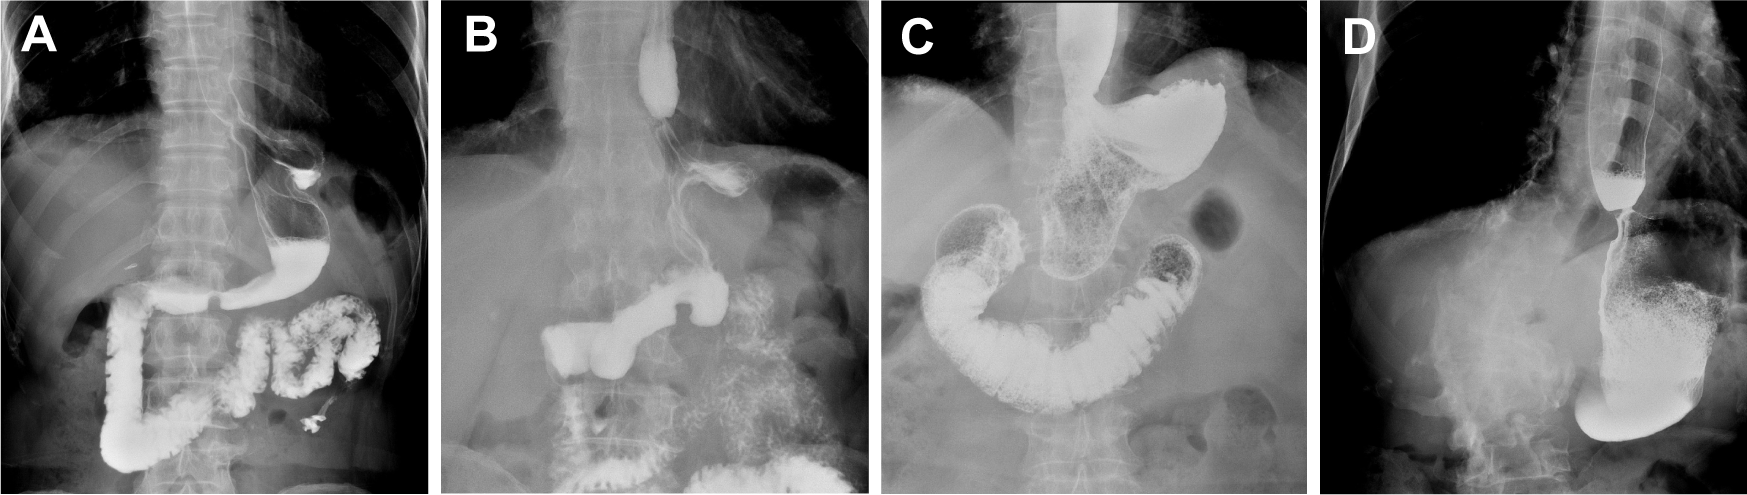

Digestive tract reconstruction (Figure 1): After lymph node dissection under laparoscopy, an auxiliary incision about 5-7cm long was made in the median of the upper abdomen for all patients to complete digestive tract reconstruction under direct vision.

Figure 1

Scope of gastrectomy and reconstruction of digestive tract. (A) Excision range of tubular esophagogastric anastomosis and design of tubular stomach shape; (B) Esophago-tubular gastric anastomosis; (C) Scope of traditional esophagogastrostomy; (D) Traditional esophagogastrostomy.